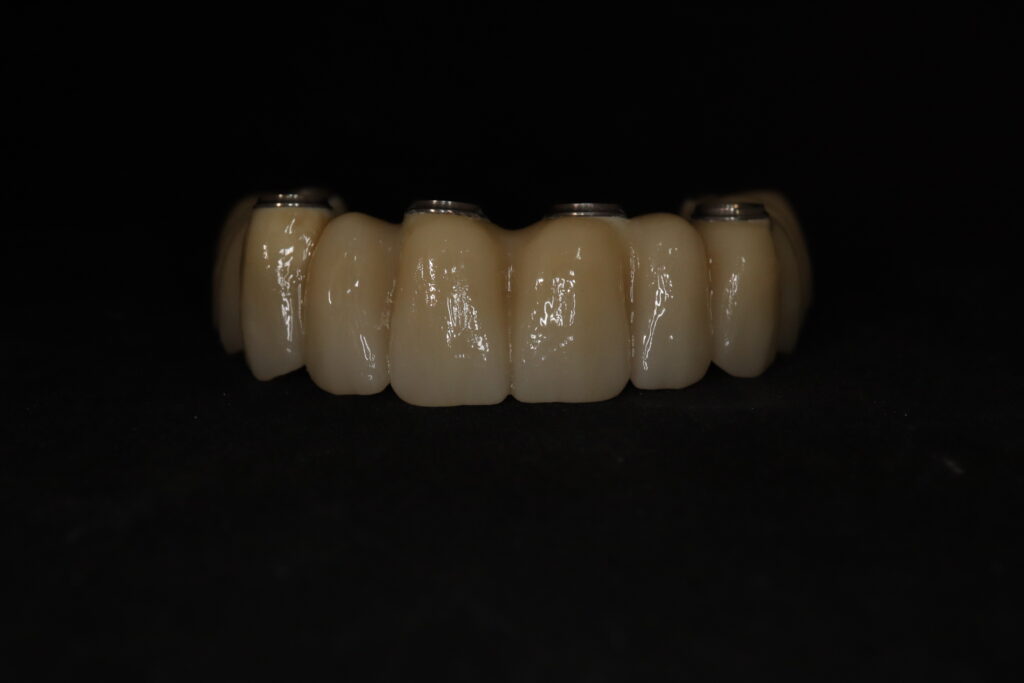

Лечение начато с выбора материала для будущей конструкции (диоксид циркония) и цвета.

Был установлен временный протез из PMMA, максимально воссоздающий форму и цвет (А3) будущей конструкции.

Спустя 20 дней был зафиксирован протез с опопрой на дентальные имплантаты из диоксида циркония.

результат имплантации